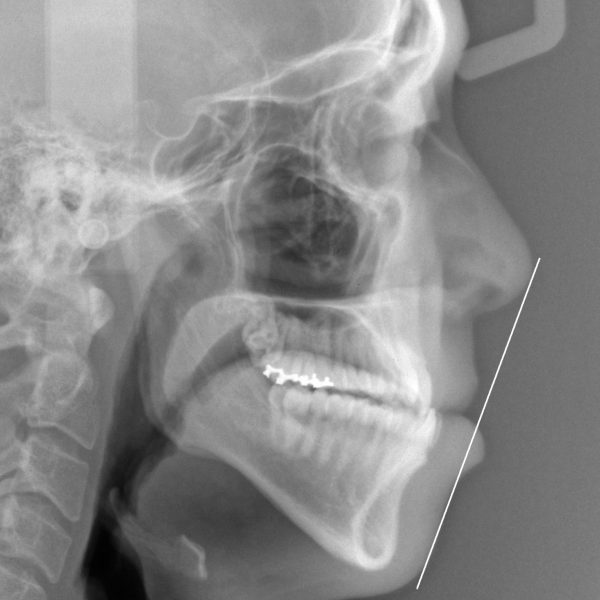

治療後のレントゲン写真です

ゴム掛けなどご本人のご協力もあり、受け口は綺麗に治りました。

骨格的なズレは治せませんでしたので理想的な仕上がりではありません。

仕上がりが甘い事を説明しましたがご本人やご家族はその変化にご満足されていました。

19歳 女性 クロスバイトを伴う骨格性反対咬合 治療期間26か月 唇側矯正装置(ホワイトワイヤー) 急速拡大装置を使用した抜歯治療 参考治療費 約72万円 (精密検査から終了まで) 矯正治療に伴う副作用の歯肉退縮、知覚過敏、失活、歯根吸収などは認められませんでした。